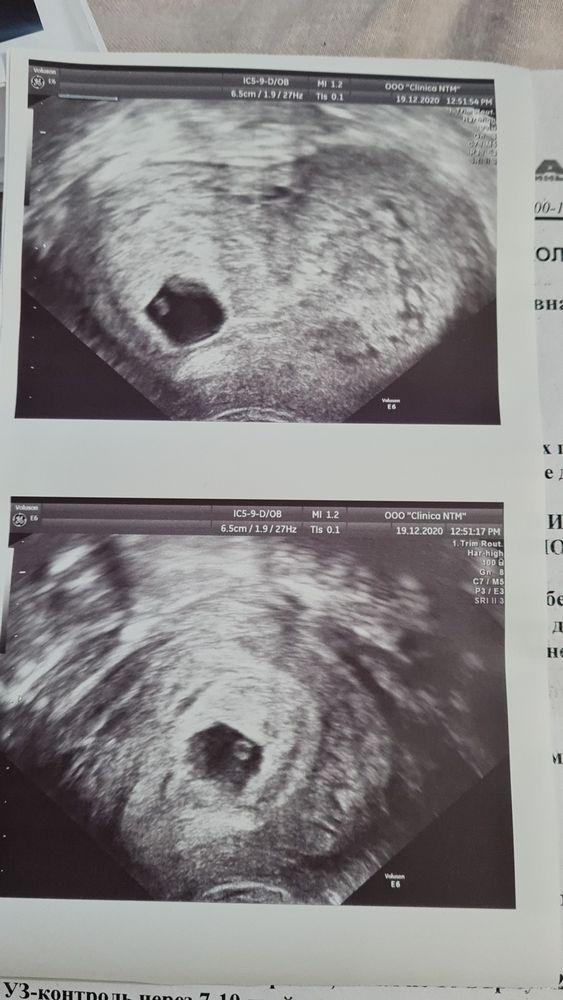

Сейчас вторая беременность, 6н2д. 3 дня назад пошла алая кровь, не прям много, на половину ежедневки. За день до этого была на узи у своего проверенного доктора - все было отлично! Я бегом на ближайшее рядом с домом узи. Все хорошо с ПЯ, ни гематом, ни отслоек. А вот во втором роге рыхлый эпителий, из него мол и кровит. И врач говорит, привыкайте, очевидно это ваша особенность- будет всю беременность кровить. Но, при этом, назначает дюфастон. Связалась с моим врачом, она отменила дюф, тк угрозы нет и назначила транексам на неделю. И оба врача мне сказали не лежать! Гулять, вести облегчённый, но в целом обычный образ жизни.